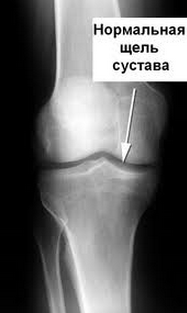

хрящом с очень гладкой, скользкой поверхностью. Хрящ позволяет концам костей двигаться против друг друга почти без трения. Коленный сустав имеет два дополнительных кусочка хрящей

(называется мениск или хрящ мениска), который помогает распределять нагрузку равномерно по колену. Нормальный коленный сустав показан на Рисунке 1.

[caption id="" align="aligncenter" width="187"]

Нормальный коленный сустав[/caption]